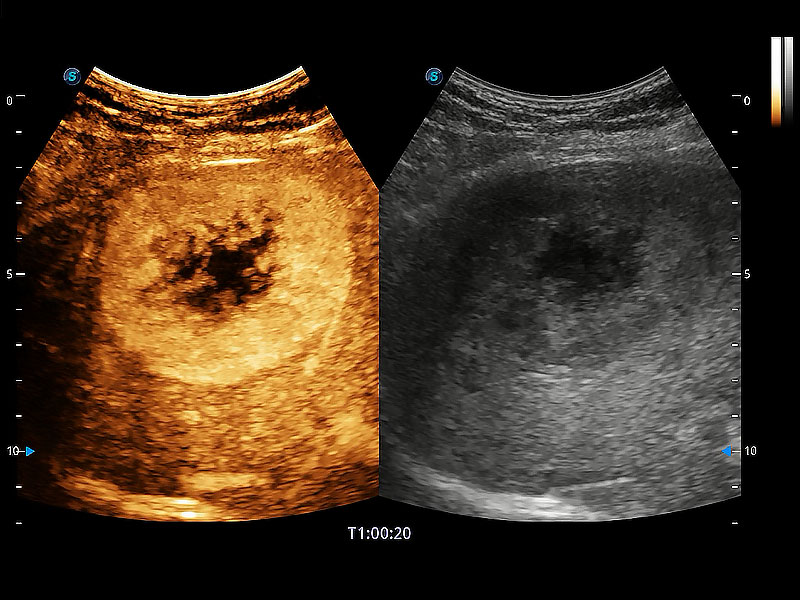

在传统二维血流成像的基础上,呈现血流的立体感,具有动感的生命力之美。即便是微小的血管也能轻松应对,提高了血流的视觉敏感性。

非线性融合造影成像充分利用谐波和基波信号,为难以观察的血流进行增强显像。可用于线阵、凸阵、微凸阵、相控阵探头。